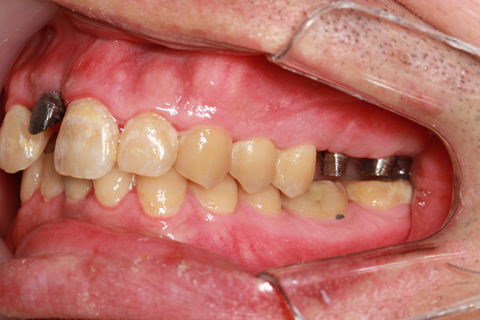

症例2

- 年齢・性別

- 57歳男性

- 治療期間

- 3ヶ月

- 抜歯

- なし

- 治療費

- 165万円

- 備考

- 左上5.6.7 及び左下6.7欠損

- 治療内容

- 左上5.6.7と左下6.7欠損部にインプラント埋入

- 施術の副作用(リスク)

- オペによる知覚障害。インプラントによる歯肉炎。インプラント脱落。